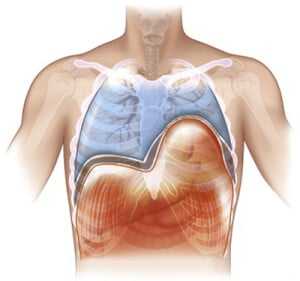

Диафрагма (diaphragma от греч. — перегородка), или грудобрюшная преграда — это куполообразная перегородка, которая разделяет грудную и брюшную полости. Выделяют центральную сухожильную и краевую мышечную части диафрагмы. Сокращаясь и расслабляясь диафрагма принимает участие в акте дыхания.

Релаксация диафрагмы - одностороннее стойкое высокое расположение диафрагмы, сохраняющей свою непрерывность и прикрепление в обычных местах.

В основе заболевания — повреждение диафрагмального нерва, при котором диафрагма расслабляется и не сокращается (т.е. наступает её релаксация). Так как в брюшной полости положительное давление, а в грудной клетке в большей части отрицательное, то органы брюшной полости давят на релаксированный купол диафрагмы. Таким образом, купол диафрагмы поднимается выше обычного, сдавливая собой соответствующее легкое. Часто заболевание так и называют — релаксация купола диафрагмы.

При диафрагмальной грыже органы брюшной полости перемещаются в грудную клетку через образовавшийся дефект, слабую зону диафрагмы или через расширенное естественное отверстие диафрагмы. В отличие от грыж при релаксации диафрагмы имеется резкое истончение ее и отсутствие мышц в целом купоне диафрагмы или в какой-либо части. Этот участок или весь купол выпячивается высоко в грудную клетку вместе с прилежащими органами брюшной полости. Выраженные грыжевые ворота при этом отсутствуют, поэтому ущемление при этом заболевании невозможно.